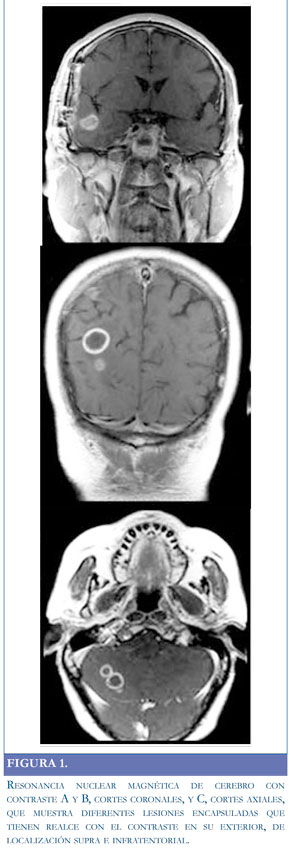

Se hospitalizó para estudio de síndrome parietal derecho y posible ataque cerebrovascular. Laboratorios iniciales, hemograma y química sanguínea, normales. Se tomó resonancia magnética de cerebro simple y contrastada, revelando múltiples lesiones de tamaños variados que comprometían ambos hemisferios cerebrales, la mayoría en el lado derecho, de apariencia redondeada y marcado edema a su alrededor, con realce en patrón anular, y una en hemisferio cerebeloso de similares características que sugieren lesiones metastásicas (Figura 1). En estudios de extensión se encontró en tomografía de tórax una opacidad en el segmento posterior del lóbulo inferior izquierdo con amputación de la luz bronquial para segmentos inferiores del lóbulo inferior. Hasta ese momento el paciente estaba enmanejo anticonvulsivante y analgésico. Se realizó biopsia de pulmón, la cual no fue conclusiva de lesión primaria infecciosa o inflamatoria, considerándose lesión cicatricial a su antecedente de tromboembolismo pulmonar. Los reportes del líquido cefalorraquídeo, incluidos citoquímico, hongos, tuberculosis, criptococo, antígenos bacterianos en la sangre; las pruebas para toxoplasmosis IgM e IgG, y VIH, fueron negativas. En el séptimo día de hospitalización la cefalea se intensificó y se encontraron signos de hipertensión endocraneana dados por diplopía y emesis. Se trasladó a unidad de cuidado intensivo y se inició manejo con esteroides y manitol a dosis adecuadas. Se estabilizó el cuadro y se decidió realizar biopsia cerebral guiada por estereotaxia (lesión parieto-occipital derecha); se aspiró material purulento, pero en el reporte definitivo no se hallan cultivos positivos ni malignidad en la patología. En ese momento el paciente no tenía diagnóstico y por resultado macroscópico de biopsia se inició antibioticoterapia endovenosa de amplio espectro: ceftriaxona, vancomicina, metronidazol, trimetroprim sulfametoxazol (TMP/SMX) y caspofungina.